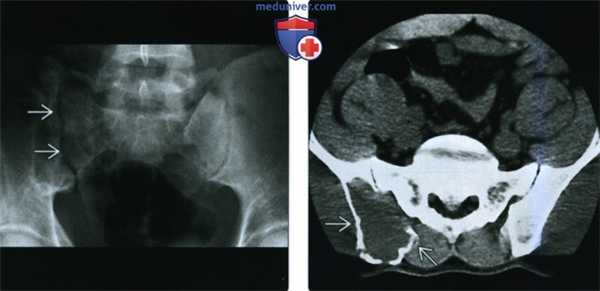

(Слева) Рентгенография в ПЗ проекции: визуализируется ЗФГ, которую легко не заметить. Правый крестцово-подвздошный сустав характеризуется абсолютной рентгенонегативностью (в сравнении с левым). Такой признак получил название «нагой крестцово-подвздошный сустав» и указывает на отсутствие задней части крыла подвздошной кости.

(Справа) КТ, аксиальная проекция, без контрастного усиления: у этого же пациента визуализируется вспученный литический очаг, замещающий костный мозг в заднем отделе крыла подвздошной кости. Патологический очаг характеризуется умеренной агрессивностью; ЗФГ является лишь одним из возможных состояний, однако во время хирургического вмешательства диагноз подтвердился.